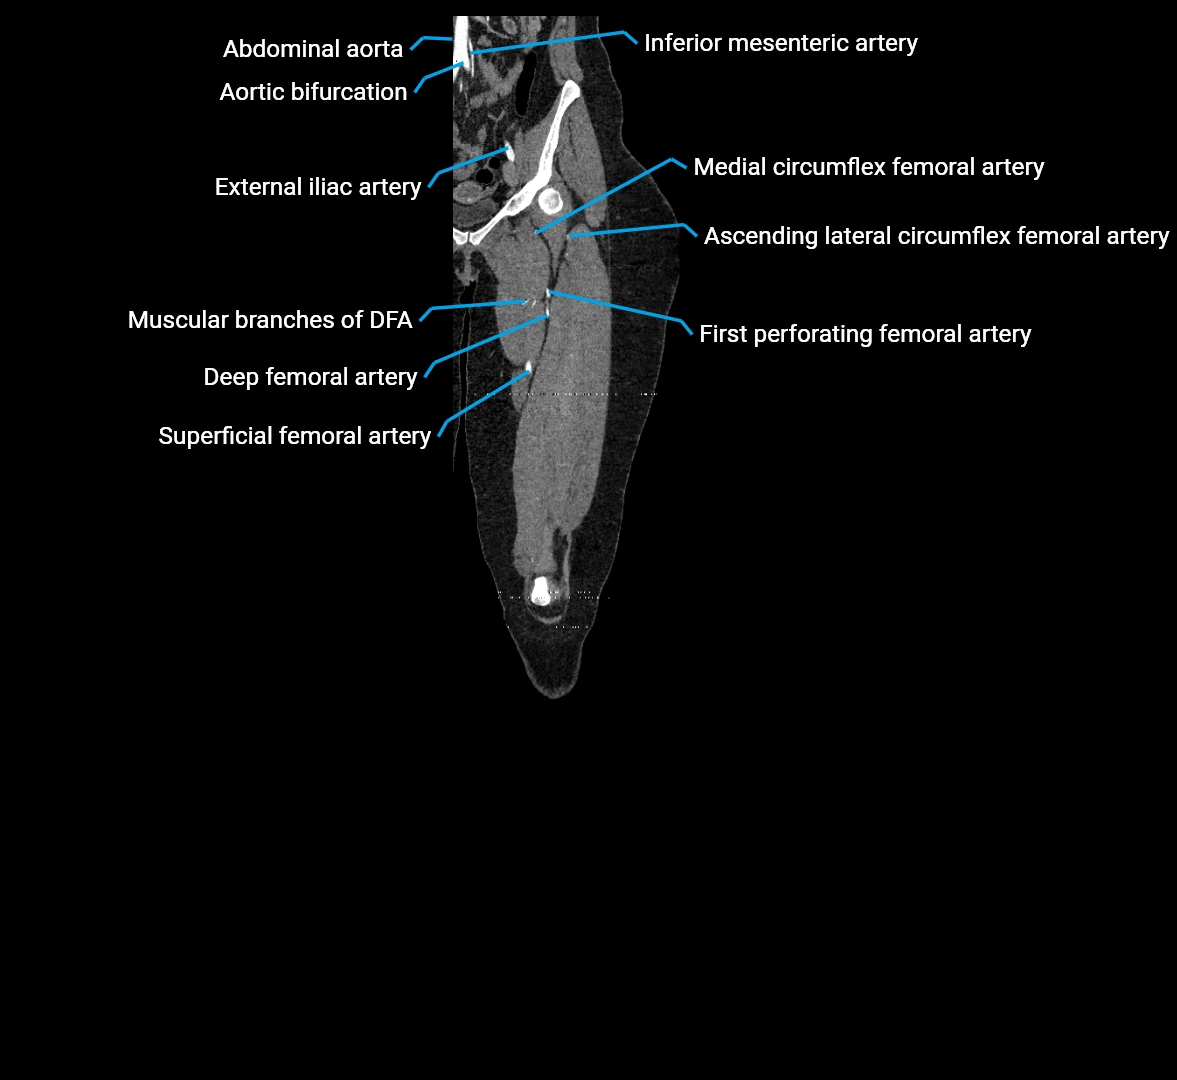

The abdominal aorta is the continuation of the thoracic aorta, beginning at the level of the aortic hiatus of the diaphragm (T12 vertebra) and terminating at the level of the L4 vertebra where it bifurcates into the right and left common iliac arteries. It lies slightly to the left of the midline and courses anterior to the vertebral bodies, surrounded by the retroperitoneal structures of the abdomen.

The abdominal aorta gives off numerous visceral and parietal branches, supplying the abdominal organs, pelvic structures, and lower limbs. It is the main conduit of oxygenated blood from the heart to the abdomen and lower body. The aorta is clinically significant as the common site of aneurysm, dissection, atherosclerosis, and traumatic injury.

Branches

• Unpaired visceral branches: celiac trunk, superior mesenteric artery (SMA), inferior mesenteric artery (IMA)

• Paired visceral branches: middle suprarenal arteries, renal arteries, gonadal arteries (testicular or ovarian)

• Parietal branches: inferior phrenic arteries, lumbar arteries, median sacral artery

• Terminal branches: right and left common iliac arteries

CT images

image